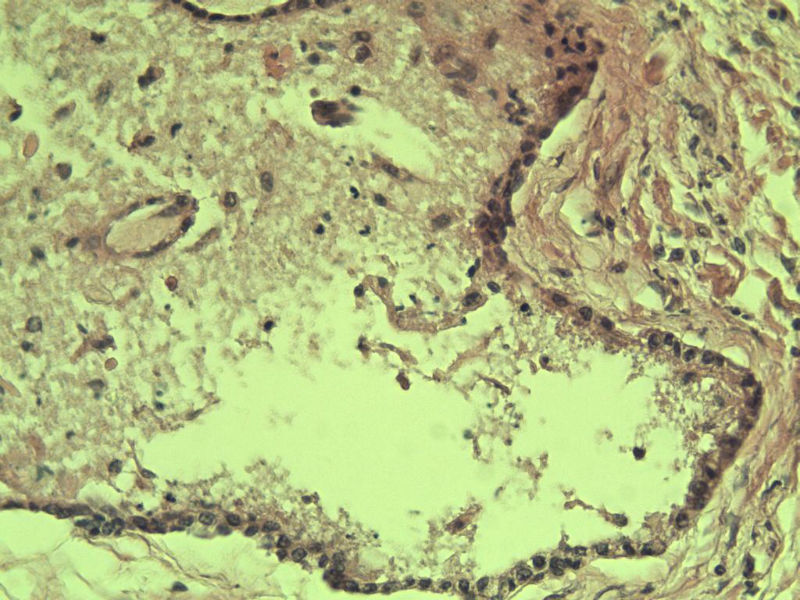

男 75岁 因排尿困难半年行前列腺切除术,体积 4 × 3 × 2.5 cm3,切面灰白,实性,质韧。请各位老师看看 有问题没? 谢谢了!

前列腺增生伴尿路上皮鳞化及Brown巢形成,未见恶性。

呈巢上皮为尿道周围前列腺组织正常现象。尿路上皮-前列腺腺体过度。

前列腺增生,有腺瘤样结节形成。